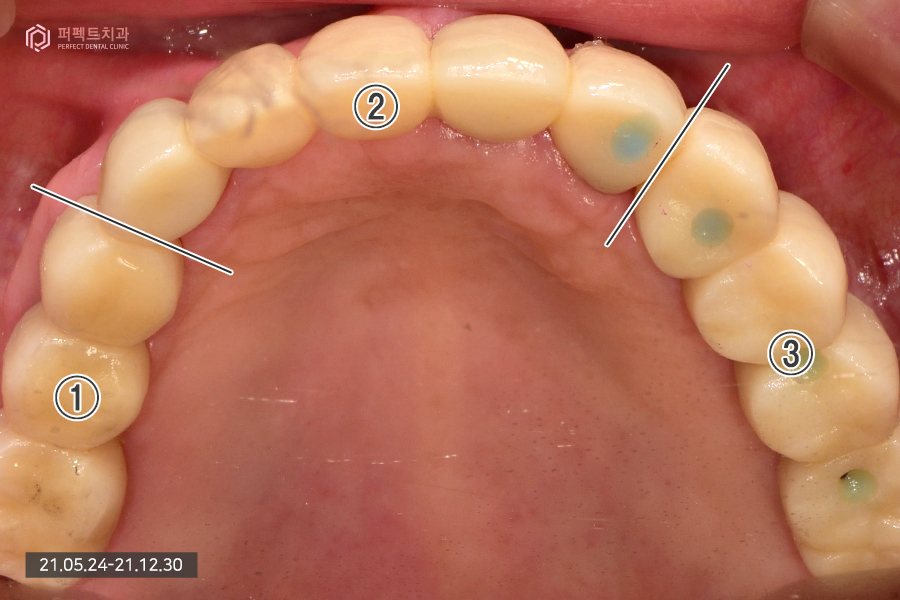

안녕하세요. 오늘은 임플란트에 관해서 살펴보겠습니다. 윗니는 전체 임플란트를 식립하는 전악 임플란트 케이스이고, 아랫니는 임플란트와 보철치료를 함께 한 케이스입니다.

내원 당시 초진 사진입니다.

80대 여성 환자분으로 연세가 많은 편이셔서 앞니는 몇 개 남지 않았고 어금니는 아예 없는 상태였습니다.

남아있는 앞니의 경우 3개가 남아있고 하나는 걸어서 사용하고 있는 상황이었는데 앞니가 심하게 흔들리고 있는 상황이라 모두 발치 하기로 결정을 하였습니다. 이런 경우 윗니는 치아가 하나도 없는 상태가 되어 전체 임플란트로 수복하게 됩니다.

아래 치아의 경우 멀쩡한 것처럼 보이지만 실제로는 그렇지 않습니다. 발치를 해야하는 치아들도 있고 치아가 없는 부분은 임플란트로 수복하기로 하였습니다.

윗니의 경우 치아가 전혀 없기 때문에 9개의 임플란트를 식립하였는데 이처럼 많은 양의 임플란트를 식립하는 경우 상황에 맞게 진료를 하게 됩니다.

전악임플란트를 하신 부분을 확인해보시면 세덩어리로 완성을 했습니다. 오른쪽 파랗게 보이는 부분은 홀을 임시로 메워둔 상태입니다. 완성된 사진을 보시면 잘 치료된 것을 보실 수 있을 것입니다.